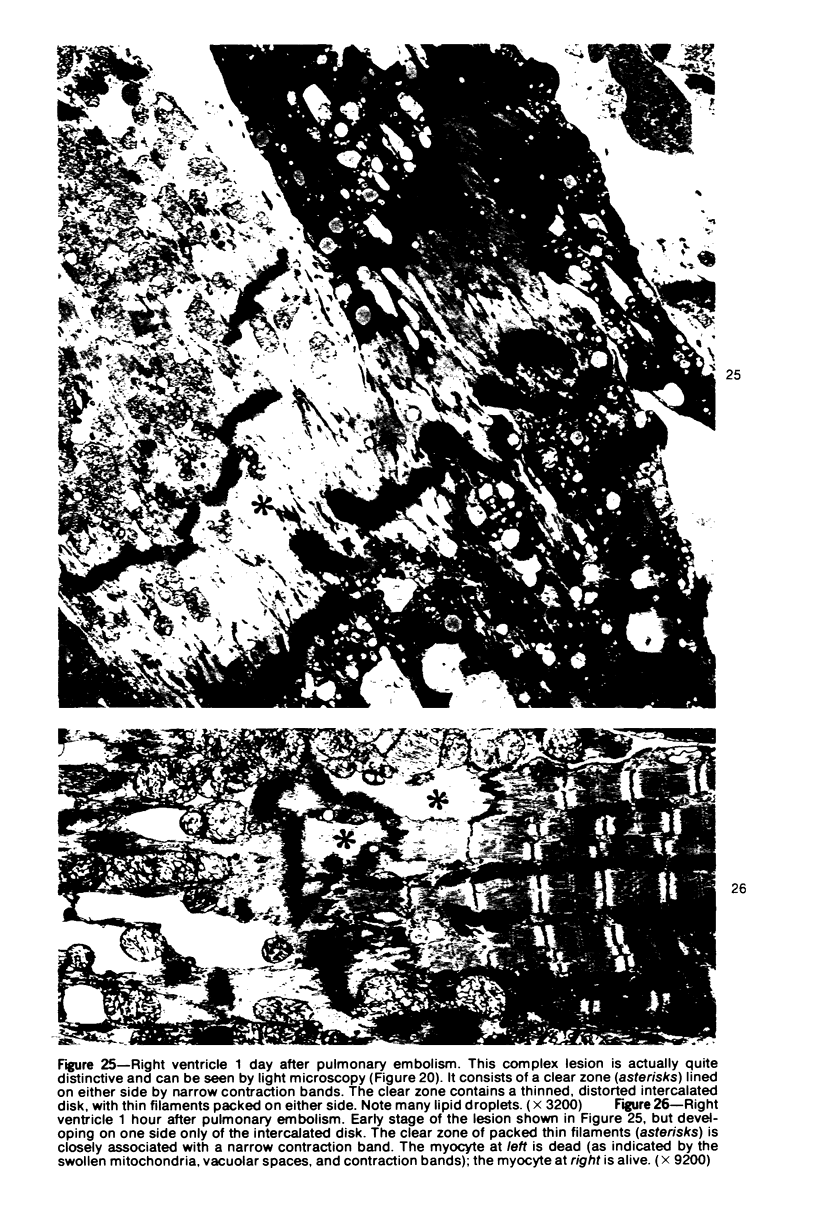

The purpose of this study was to find out whether acute massive pulmonary embolism can produce myocardial changes visible by light and electron microscopy. Ww therefore produced pulmonary embolism in rats using plastic microspheres (diameter, 15 +/- 5 mu). Two experimental protocols were used: lethal embolism, with a dose of microspheres known to kill in 3 to 15 hours (these rats were killed after 1 hour), and sublethal embolism, with a dose compatible with 100% survival (these rats were killed after 24 hours). In both groups, the left ventricle was normal. The right ventricle showed two tyes of changes: a) A distinctive lesion of the myocytes, more diffuse after lethal enbolism and different from the "zonal lesion" of shock. It consisted primarily in a localized shredding of the myofibrillar system; hence, the name shredding is proposed. Earlier stages of this lesion were represented by focal dissolution of the Z line (Z lysis). The pathogenesis of these lesions appeared to be primarily mechanical. b) Necrosis was already apparent at 1 hour and was more extensive after 24 hours. The pathogensis of the necrotic lesions is best explained by a temporary ischemia followed by delayed reflow; a possible potentiating role of endogenous catecholamines cannot be excluded. Most capilaries in the necrotic foci remained functional; this explains the rapid rate of the healing process of such lesions. A comparison is drawn between the observed foci of necrosis and the human myocardial lesions knowns as "miliary infarcts" and "myocytolysis." It is proposed that a factor common to all three is the preservation of the microcirculatory vessels and that our experimental model helps illuminate the pathogenesis of the human lesions. It is concluded that the right ventricle of acute cor pulmonale may develop cellular changes with a complex pathologenesis (mechanical, ischemic, and possibly hormonal). The nature of the changes found in our model could represent the morphologic substrate of right-sided failure; it can be correlated with the electrocardiographic abnormalities found in the comparable human condition.